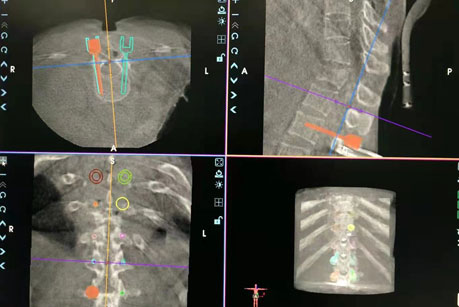

(术中手术路径规划及实施手术)

侯克东带领手术团队首先完成手术路径的规划,并操作机器人进行手术三维定位,实施置钉。三维扫描影像显示螺钉位置精准无误,完全符合手术规划,最后圆满完成手术。此次手术的成功,意味着骨科机器人手术可以使很多高难度、高风险及复杂脊柱外科手术变得更加安全、高效、微创及智能。